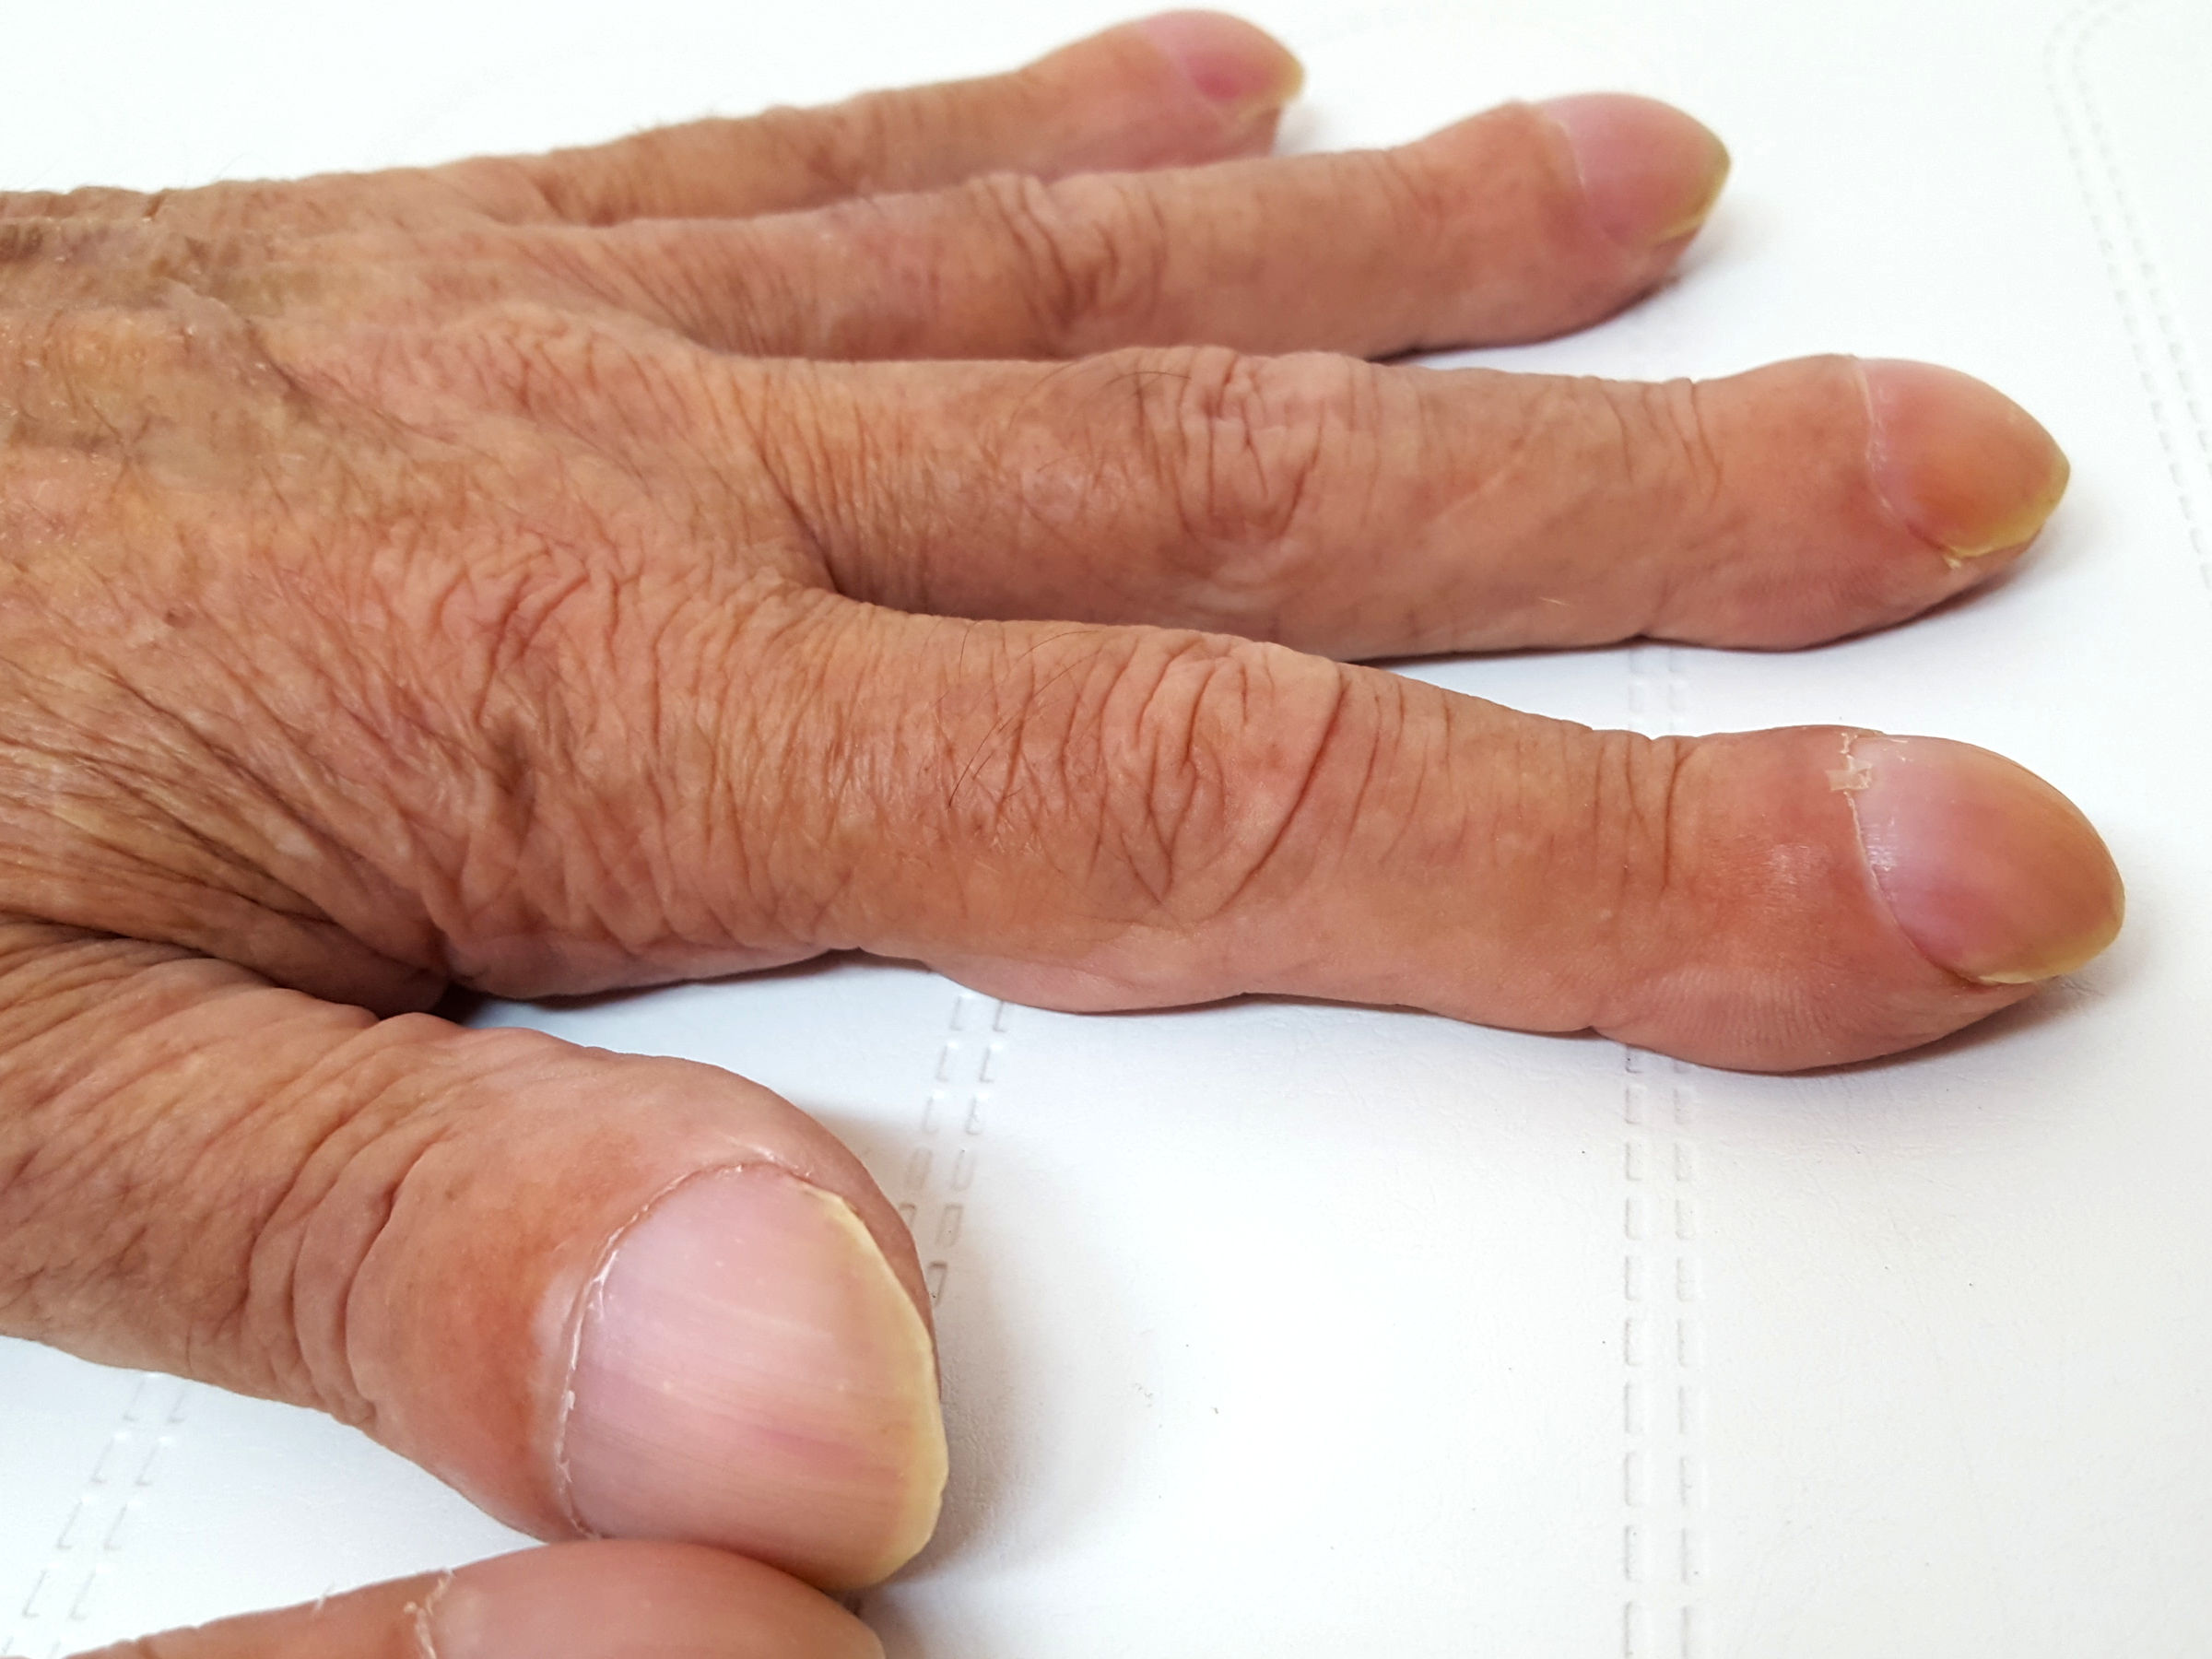

Een patiënt met deze afwijking heeft bolle nagels met bredere vingertoppen en geen nagelriemen. Je longen hebben een bijzondere anatomie en bevinden zich in je borstkas en worden omringd door je ribben. Dat wil zeggen dat we uit een verkleurde iris, of blauwgroene pus, of een bolle nagel, een hele wereld aan pathologie.

Enkele longaandoeningen, hartaandoeningen, huidaandoeningen en maagdarmaandoeningen gaan gepaard met dit symptoom. Mensen met hele bolle nagels, ook wel trommelstokvingers of horlogenagels genoemd, hebben nagels die over de vingertop heen groeien. Erg bleke of witte nagels ontstaan door ouder worden, maar het kan ook een teken zijn van serieuze aandoeningen, zoals bijvoorbeeld bloedarmoede, leverziekte, voedingsstoffentekort en hartfalen.

Trommelstokvingers of horlogeglasnagels zijn bolronde nagels en eindkootjes, welke worden geassocieerd met interne aandoeningen die gepaard gaan met onvoldoende doorbloeding (ischemie). But not sure were to start?. Normaalgezien is de afwijking niet pijnlijk, maar soms presenteert een patiënt zich met pijn in de vingertoppen.

Vormveranderingen (bolle, holle en kromme nagels) Trommelstokvingers (clubbed fingers), bolle nagels Bij trommelstokvingers zijn de nagels bolvormig, de hele eindkootjes zijn verdikt. Neem een kijkje op de beste bolle nagels longen in de foto’s hieronder en krijg ideeën voor uw fotografie!!!. De nagel drukt dan tegen de zijkant van de nagelwal.

Het is niet onverstandig om een afspraak te maken met uw huisarts wanneer u last heeft van bolle nagels. Bolle nagels ontstaan doordat u te weinig zuurstoftoevoer naar uw vingertoppen heeft. 4/mai/18 - Neem een kijkje op de beste bolle nagels longen in de foto’s hieronder en krijg ideeën voor uw fotografie!!!.

Bij aandoeningen van het hart, de longen, grote bloedvaten of het maag-darmstelsel kan het zuurstofgehalte in het bloed afnemen. De vingertoppen zijn verdikt, warm en rood. De longen zorgen ervoor dat u iedere vier seconden die zuurstof krijgt.

Een 62-jarige man vertelt dat zijn nagels steeds boller worden en zijn vingertoppen steeds dikker. De arts schuift een buigzame slang met een kleine camera via uw mond of neus in de longen. Als dit niet op tijd verholpen wordt kan dit uitmonden in een ontsteking.

De vingertoppen zijn verdikt, warm en rood. Dat is meer dan .000 keer per dag of acht miljoen keer per jaar. Dan is het een aangeboren kenmerk.

Dunne bolle nagels Home//Forum//Handen & voeten//Dunne bolle nagels googletag.cmd.push(function() { googletag.display('div-gpt-ad-dokter_header');. Het ontstaat door een te laag zuurstofgehalte in je bloed, meestal veroorzaakt door long- of hartaandoeningen. Blush Pink Oval Nails Image source.

Bolle nagels komen voor als symptoom bij bepaalde longziekten en aandoeningen van het hart. That’s because of the flexibility they can give you in expressing your own idea. Als de nagels vooral wit zijn met donkere randen, dan kan dit wijzen op leverproblemen zoals hepatitis.